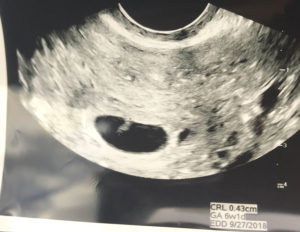

Family Super Happy With Reversal Baby On The Way!

Super Happy With Reversal Results!

I am due September 2018! I had my surgery October 2017.

Thanks so much again. My family is super happy!

Patient age: 27

Tubal ligation type: Resection (tied or cut)

Patient hometown: Washington, DC